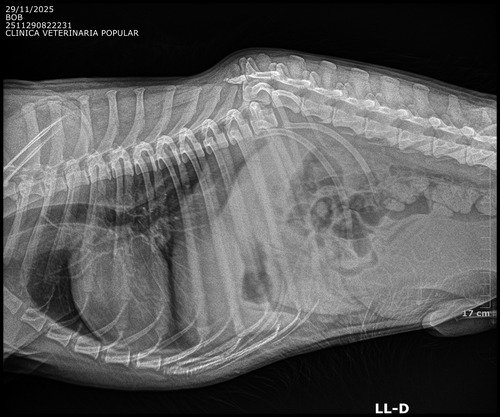

Meu nome é Maria de Fátima e venho compartilhar a história de Bob, um cãozinho que sofreu um grave acidente e fraturou a coluna vertebral.

Infelizmente, devido a gravidade da leão, o Bob não conseguirá mais andar sozinho. Para evitar dores crônicas e o risco de infecção ele precisa urgentemente de uma cirurgia que custa R$3.500,00.